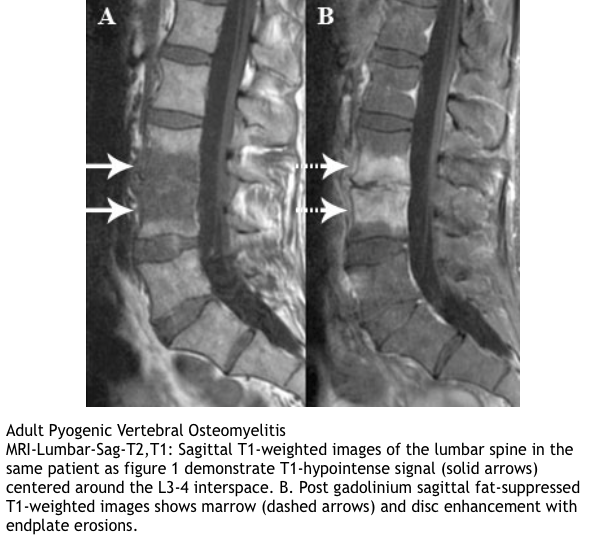

MRI